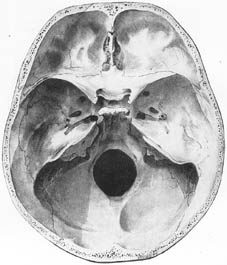

上蓋の内側面に前後に走る(上)矢状洞溝があり、両側に多くのクモ膜顆粒小窩がある。下壁は内頭蓋底といい、前中後の3窩に分かれている。

(1)Fossa cranii (cranialis) anterior(前頭蓋窩)Anterior cranial fossa

3窩の内で最も浅い、大脳前頭葉の容れるところである。正中部は鼻腔の上壁に当たり、篩骨の篩板でできている。篩板に篩孔があり、これにより鼻腔と交通している。

(2)Fossa cranii (cranialis) media(中頭蓋窩)Middle cranial fossa

正中部は蝶形骨の体で中頭蓋窩を左右の両部に分けている。蝶形骨体の上面は鞍状にくぼんでおり、ここをトルコ鞍といい、中央部に下垂体を入れる下垂体窩がある。トルコ鞍の上外方には視神経管があり、眼窩に通じている。蝶形骨の大翼と小翼との間には上眼窩裂があって、これも眼窩に通じている。大翼には正円孔・卵円孔・棘孔が一列に並んでおり、前者は翼口蓋窩に、後二者は側頭下窩に通じている。錐体の先端と蝶形骨体との間には破裂孔があって、ここに頸動脈管が開口している。

(3)Fossa cranii (cranialis) posterior(後頭蓋窩)Posterior cranial fossa

おもに側頭骨の鱗部と後頭骨から作られている。錐体後面の中央には内耳道があり、外方に走って内耳の内側壁に達する。後頭蓋窩の中央には大後頭孔があって、前方に斜台であり、大後頭孔の前外縁に舌下神経管の内口がある。後頭鱗の内面中央には内後頭隆起がある。(上)矢状洞溝はここに始まって頭蓋上壁の正中を前頭部まで走り、横洞溝はこれから左右に横走し、側頭骨乳突部の内面をS状(S状洞溝)に曲がって頸静脈孔に達している。